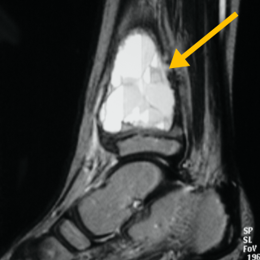

Radiographic imaging is used to help form a diagnosis of ABC. These include X-Ray, MRI, CT and Bone Scans

An example of an ABC X-Ray (Figure 1A) and an MRI (Figure 1B) with fluid fluid levels are shown.